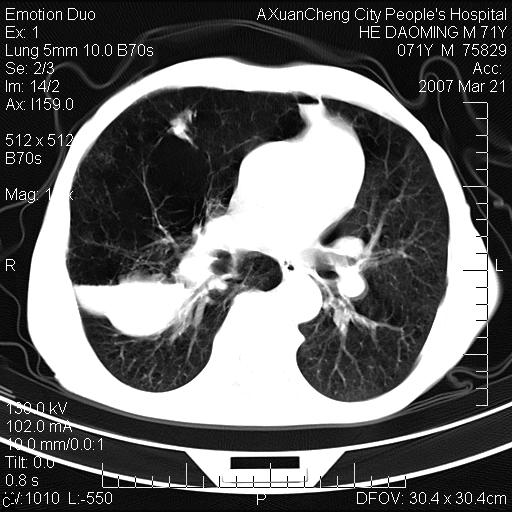

标题: CT7269:[原创] 咳嗽,咳痰,大家讨论右肺病变的部位 [打印本页]

标题: CT7269:[原创] 咳嗽,咳痰,大家讨论右肺病变的部位

1.慢支肺气肿 肺心病 肺大泡;2.叶间裂积液,前胸膜粘连

右侧相当于叶间软组织样密度ct值约50hu,请大家讨论是什么性者病变

考虑:慢性支气管炎合并全小型肺气肿、肺大泡、间质纤维化、感染,右斜裂积液。

考虑慢支,肺气肿,肺大泡,间质纤维化;右侧斜裂液气胸考虑(可能因为肺大泡破裂破入斜裂所致).

考虑病变以右上中肺多发肺大泡为主并感染。请结合临床考虑慢支肺气肿,肺心病。

1双肺慢性支气管炎并全小叶型肺气肿肺大泡2间质性纤维化3右侧斜裂积液

考虑:慢性支气管炎合并右侧全小型肺气肿、肺大泡并感染、双肺间质纤维化,右斜裂积液。

如果患者变化一下体位扫描可分辨液平与斜裂的关系。